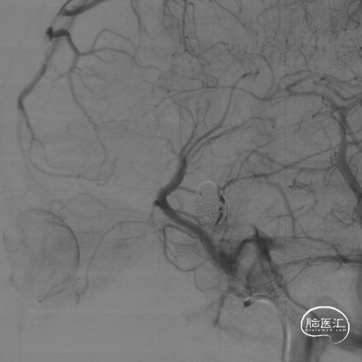

撤掉SL-10微导管后XT-27微导管置于大脑中动脉。

选择Evolve 4.5/20,输送到位,通过推拉结合方式释放。

支架远端定位于脉络膜前动脉以近,近端位于海绵窦段。

动脉瘤大部栓塞,瘤颈部造影剂滞留。

Vaso CT重建 支架打开、贴壁良好。